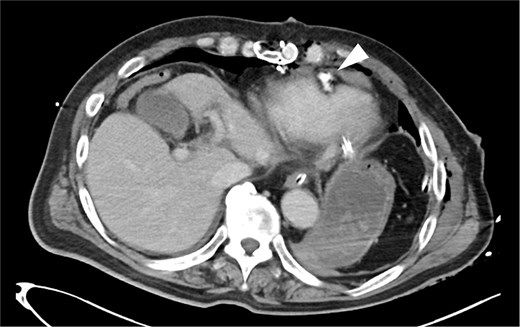

The external appearance of the wound did not clearly reflected the extent or nature of internal injury. Based on the presumptive diagnosis of intra-abdominal injury, an emergency exploratory laparotomy was performed. The initial exploration by general surgeons revealed no evidence of intra-abdominal organ damage. Given the suspicion of diaphragmatic penetration and intrathoracic hemorrhage, the cardiac surgery team proceeded with a left thoracotomy. This revealed dark, reddish fluid suggestive of pericardial hemorrhage. Suspecting obstructive shock due to cardiac tamponade, the surgical approach was converted to a median sternotomy. Upon opening the pericardium, a significant hemopericardium was identified, and active bleeding from the anterior wall of the right ventricle was successfully controlled using 3-0 polypropylene sutures with pledgets (Fig. 2). Standard chest closure and wound closure were subsequently performed, and the patient was transferred to the intensive care unit in a stable condition. The postoperative course was uneventful. Follow-up computed tomography (CT) imaging demonstrated no pericardial effusion or other complications (Fig. 3). The patient recovered favorably and was discharged home one month after surgery.

Postoperative CT findings. No evidence of pericardial effusion was observed, and the surgical site was hemostatic (arrowhead).